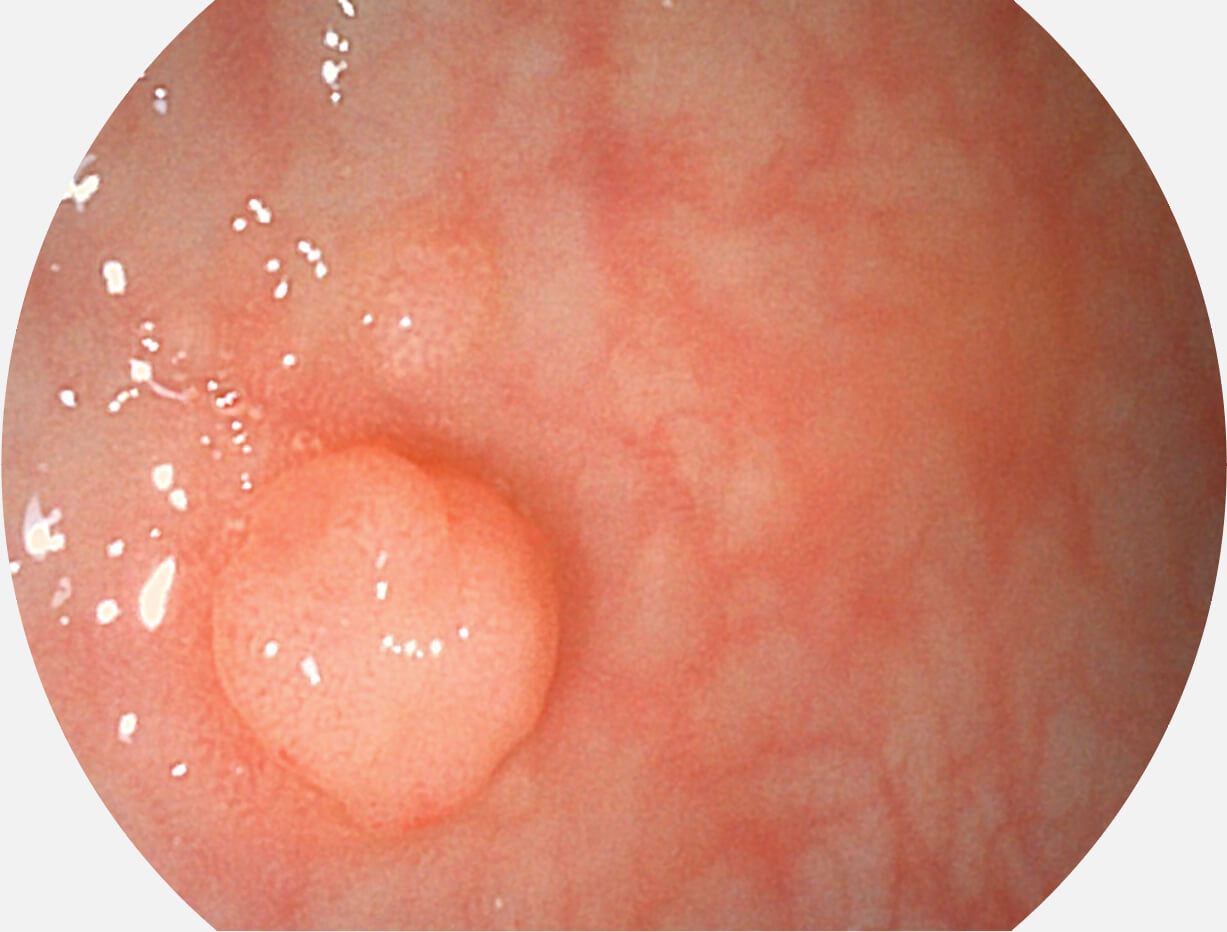

图像具有高亮度、高黏膜血管颜色对比度的特点,且不改变粘液、食物残渣、粪便的基本颜色,可在中远景下进行观察,助力消化道早期疾病的诊断。

白光图像

SFI图像